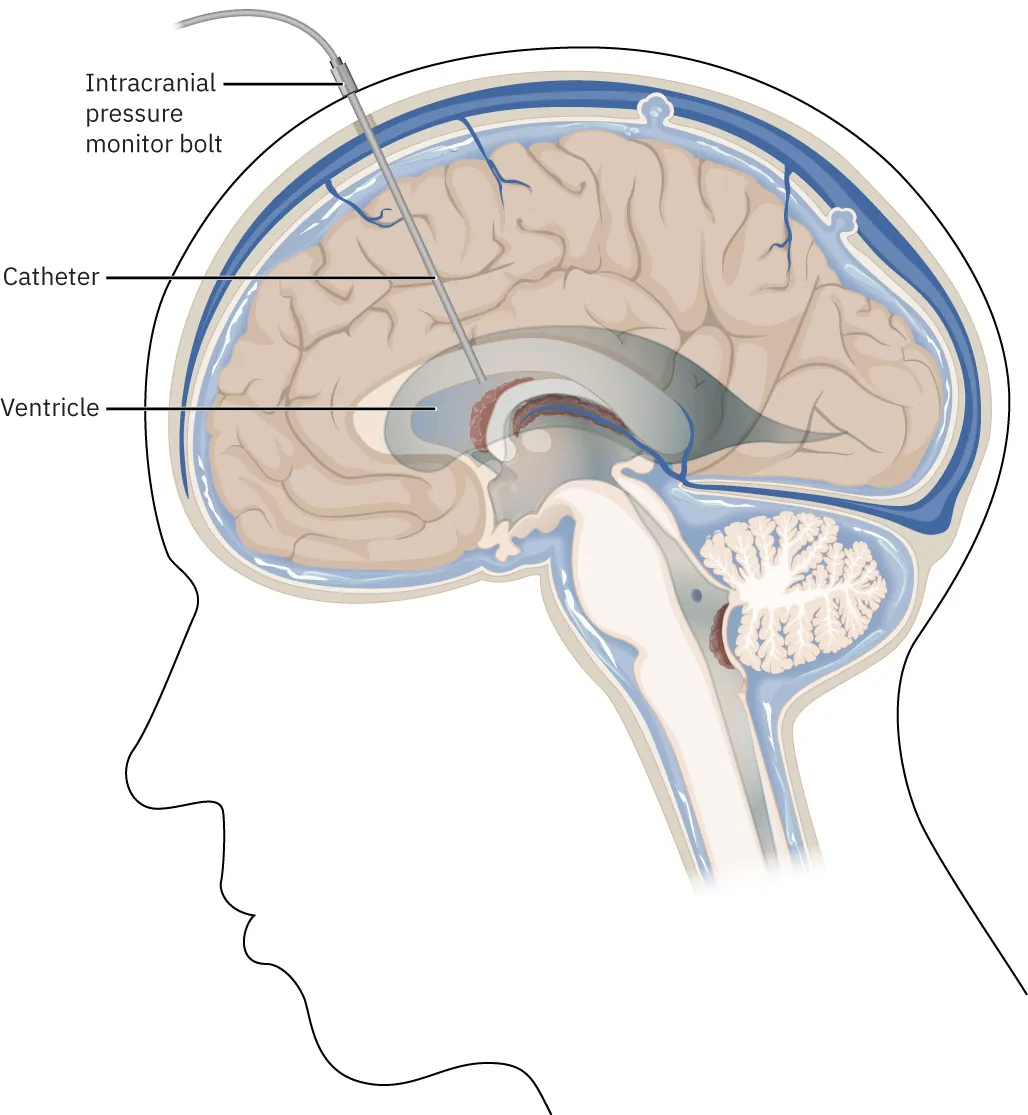

Finally, the nonsurgical interventions associated with treating increased ICP are raising the head of the bed and administering osmotic diuretic drugs like mannitol. For continuous ICP monitoring, the best method is an invasive technique called a ventriculostomy (Figure 15.10). During a ventriculostomy, a hole is drilled through the skull and a catheter for measuring pressure is placed directly into the ventricle. The result is a display on a monitor that reads the intracranial pressure. This is often coupled with an external ventricular drain (EVD) that provides a way to drain cerebrospinal fluid (CSF) from the ventricles if the ICP becomes too high.

A diagram showing a ventriculostomy, labeling Intracranial pressure monitor bolt, Catheter, and Ventricle.

Figure 15.10 A ventriculostomy is an invasive technique for monitoring ICP. It can also include a drainage system (EVD) to drain CSF if needed. (credit: modification of work from Anatomy and Physiology 2e. attribution: Copyright Rice University, OpenStax, under CC BY 4.0 license)